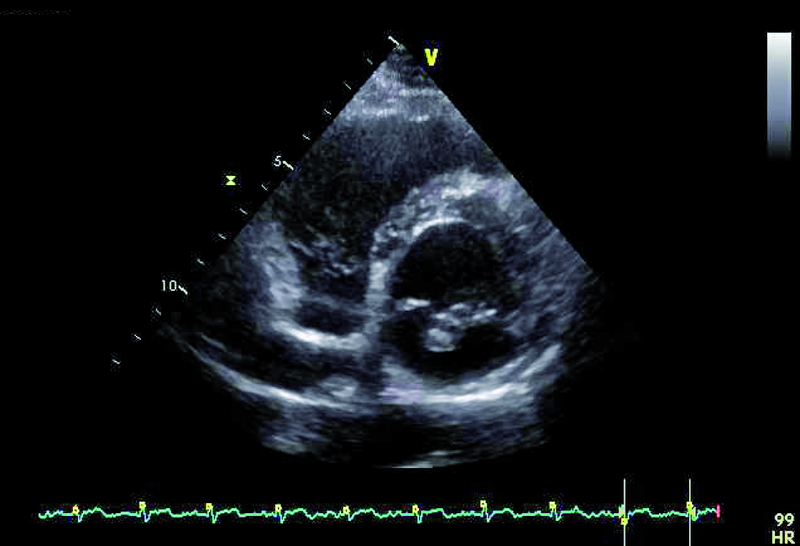

Badanie przezklatkowe, które jest badaniem pierwszego wyboru w przypadku podejrzenia zapalenia wsierdzia, potwierdza obecność dodatkowego echa na strukturach zastawki mitralnej (ryc. 1, 2). Wskazanie konkretnego elementu zastawki, stanowiącego podstawę dla rozwijającej się wegetacji, jest jednak trudne. Badanie przezprzełykowe pozwala lepiej zobrazować punkt wyjścia wegetacji, stopień destrukcji płatka i istotność fali zwrotnej. Szczegółowa ocena zastawki wymaga zastosowania wielu projekcji i płaszczyzn obrazowania, a także znajomości anatomii i relacji przestrzennych poszczególnych struktur. Kryterium orientacyjnym w ocenie jest to, że płatek przedni zastawki mitralnej leży zawsze blisko aorty. Jeśli aorta jest widoczna, zazwyczaj sąsiadują z nią segmenty A1 i A2. Blisko uszka lewego przedsionka leżą natomiast segmenty płatka przedniego i tylnego: A1 i P1. Zawsze warto uwzględnić projekcję i płaszczyznę, w jakich zastawka jest oceniana. Jeśli jest to projekcja dwujamowa z widocznym uszkiem lub jego częścią, to układ segmentów, rozpoczynając od uszka, jest następujący: P1, A2 i P3. Dodatkowe echo zatem widoczne przy spoidle tylno-przyśrodkowym w obrazowaniu przezprzełykowym (ryc. 3, 4) związane jest z segmentem najbardziej dystalnym w stosunku do uszka, a więc z segmentem P3.